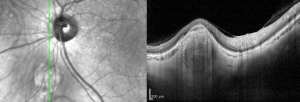

Optical coherence tomography (OCT) has led to new understanding of FSN including the anatomic origin within the sclera (instead of the choroid as previously described). Most lesions have a dome-shaped contour, but nodular or volcanic shapes have also been noted. The overlying choroid is displaced and compressed against Bruch's membrane. The resulting thinning or absence of the overlying choroid is the likely cause of their yellow-white, atrophic appearance on fundoscopic exam. OCT angiography will show the lesions to be avascular and most will demonstrate hyperautofluorescence on fundus autofluorescence (FAF) imaging.[4]